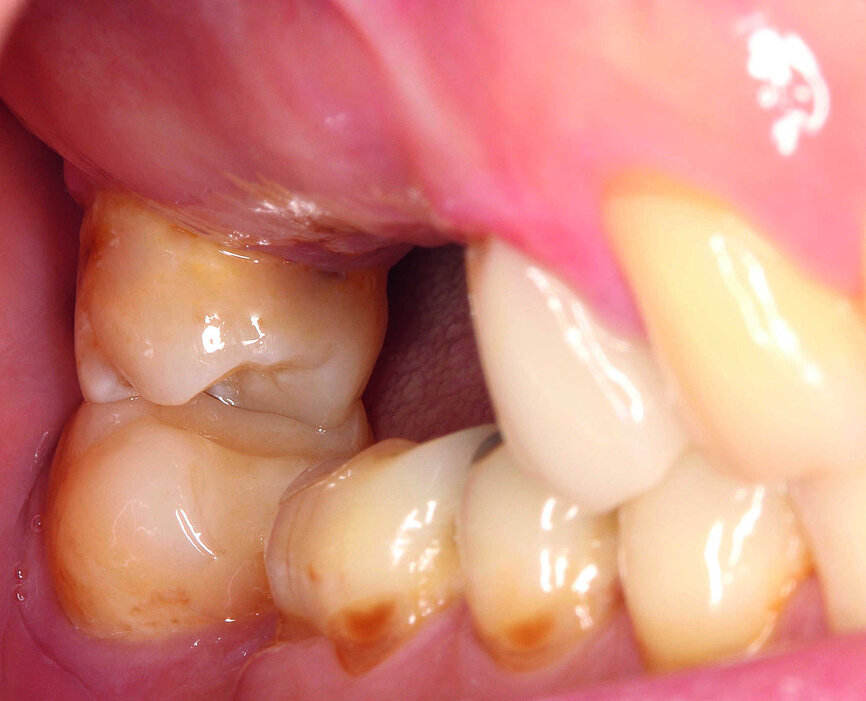

En janvier 2015, le patient, âgé de 42 ans, souhaitait une restauration globale et sans métal de sa denture, dont certaines dents manquaient ou nécessitaient un traitement (Fig. 1). Le bridge qu’il avait d’abord porté pour remplacer les dents absentes, 15 à 17, avait été retiré quelques années auparavant par le chirurgien-dentiste habituel du patient, et depuis lors l’espace n’avait jamais été restauré par une autre prothèse (Fig. 2). Le patient s’était déjà informé sur les possibilités de restauration et souhaitait le remplacement de ses dents manquantes par des implants en céramique. L’évaluation des radiographies indiquait une largeur osseuse adéquate, mais une hauteur réduite due à une résorption de l’os alvéolaire et une pneumatisation du sinus maxillaire. Une large bande de muqueuse attachée était présente dans la zone prévue pour l’émergence des implants. Selon les critères de classification du risque SAC (Simple - Avancé - Complexe) de la Société suisse d’implantologie orale, le cas était de niveau A. (Tableau 1).

Figs. 1 et 2 : Situation intra-orale initiale.